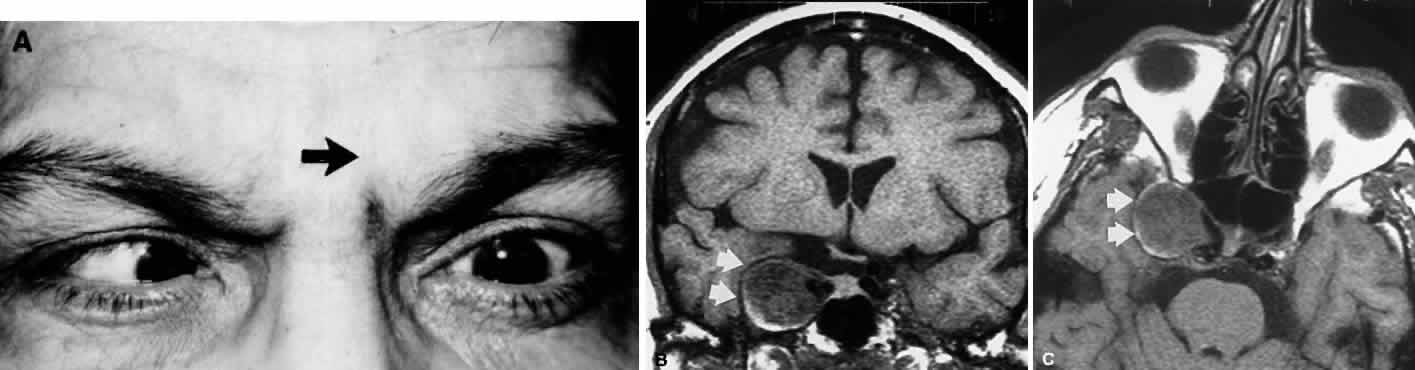

Primary neurinoma of the oculomotor nerve is a relatively rare lesion that should be considered in children or young adults with insidious third nerve palsy. These may occur in the cavernous or interpeduncular portion of the nerve (Fig. 13).99,100

Fig. 13. Insidiously progressive third nerve palsy due to oculomotor neurinoma (arrows) in 16-year-old girl. MRI T-1, enhanced axial (top) and coronal (bottom) sections.